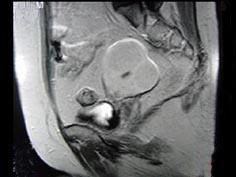

问题 55岁女性患者,绝经后阴道排液半年余,行MRI检查,如图所示,最佳答案是 ( )

选项 A、子宫肌瘤 B、子宫内膜癌 C、子宫颈癌 D、正常子宫 E、子宫内膜异位症

答案 B